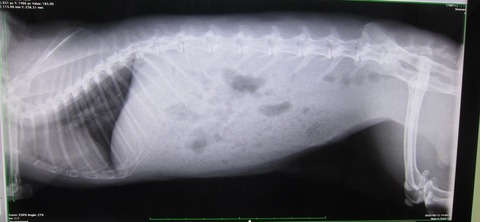

はい、もしや痩せたとか?って体重測定の比較です、